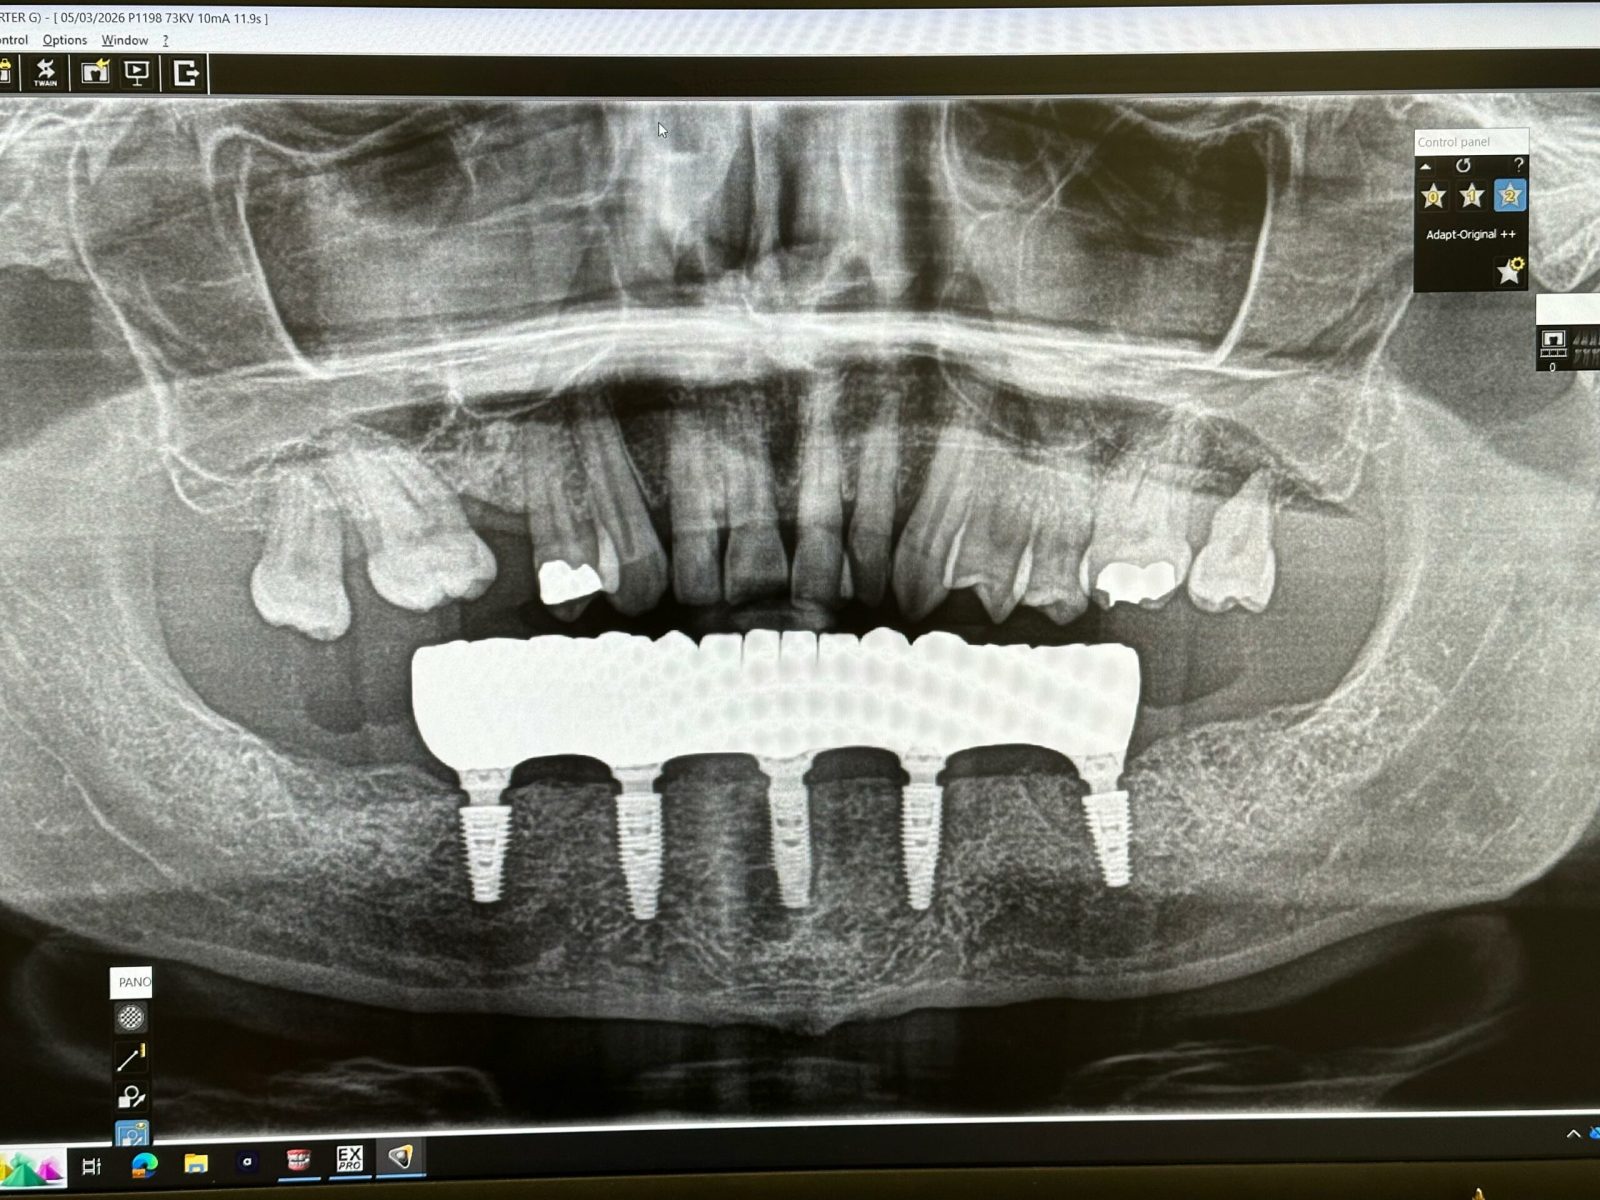

Implants placed using a digitally planned stackable surgical guide following alveolectomy, ensuring ideal positioning and a stable foundation for full-arch restoration.